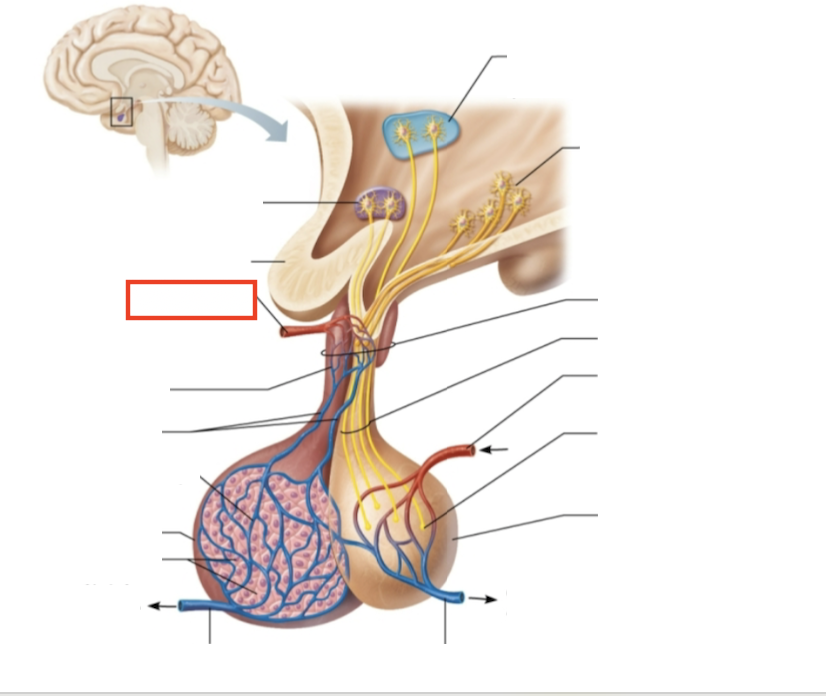

What structure is highlighted?

testes (male)

What structure is highlighted?

hypothalamic neurons in the paraventricular nuclei

What structure is highlighted?

neurons in the ventral hypothalamus

What structure is highlighted?

infundibulum (connecting stalk)

What structure is highlighted?

hypothalamic-hypophyseal tract

What structure is highlighted?

inferior hypophyseal artery

What structure is highlighted?

neurohypophysis (storage area for hypothalamic hormones)

What structure is highlighted?

posterior pituitary

What molecules are produced here?

oxytocin, ADH

What structure is highlighted?

venule

What structure is highlighted?

venule

What molecules are produced here?

TSH, FSH, LH, ACTH, GH, PRL

What structure is highlighted?

secretory cells of adenohypophysis

What structure is highlighted?

anterior pituitary

What structure is highlighted?

secondary capillary plexus

What structure is highlighted?

hypophyseal portal veins

What structure is highlighted?

primary capillary plexus

What structure is highlighted?

superior hypophyseal artery

What structure is highlighted?

superior hypophyseal artery

What structure is highlighted?

optic chiasma

What structure is highlighted?

hypothalamic neurons in the supraoptic nuclei